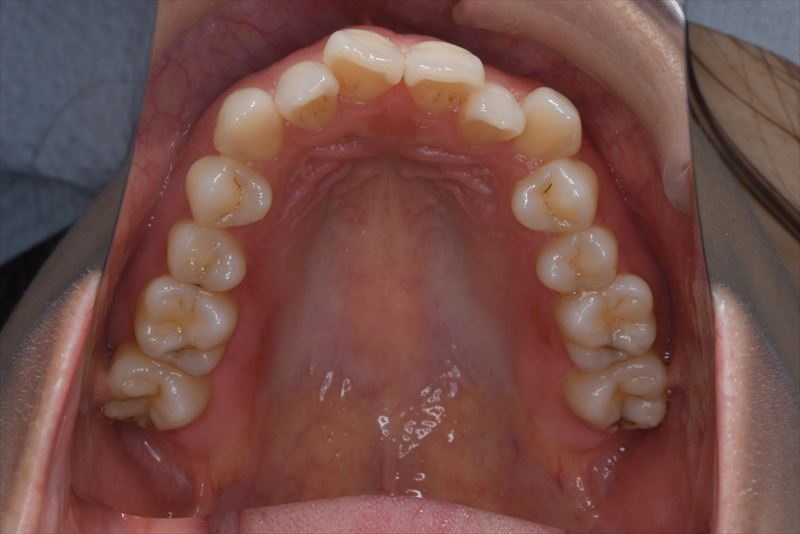

治療後

臼歯のみの咬合、口唇の閉鎖が難しい状況でした。抜歯を行い前歯を牽引することで、良好な側貌と緊密な咬合を獲得できました。